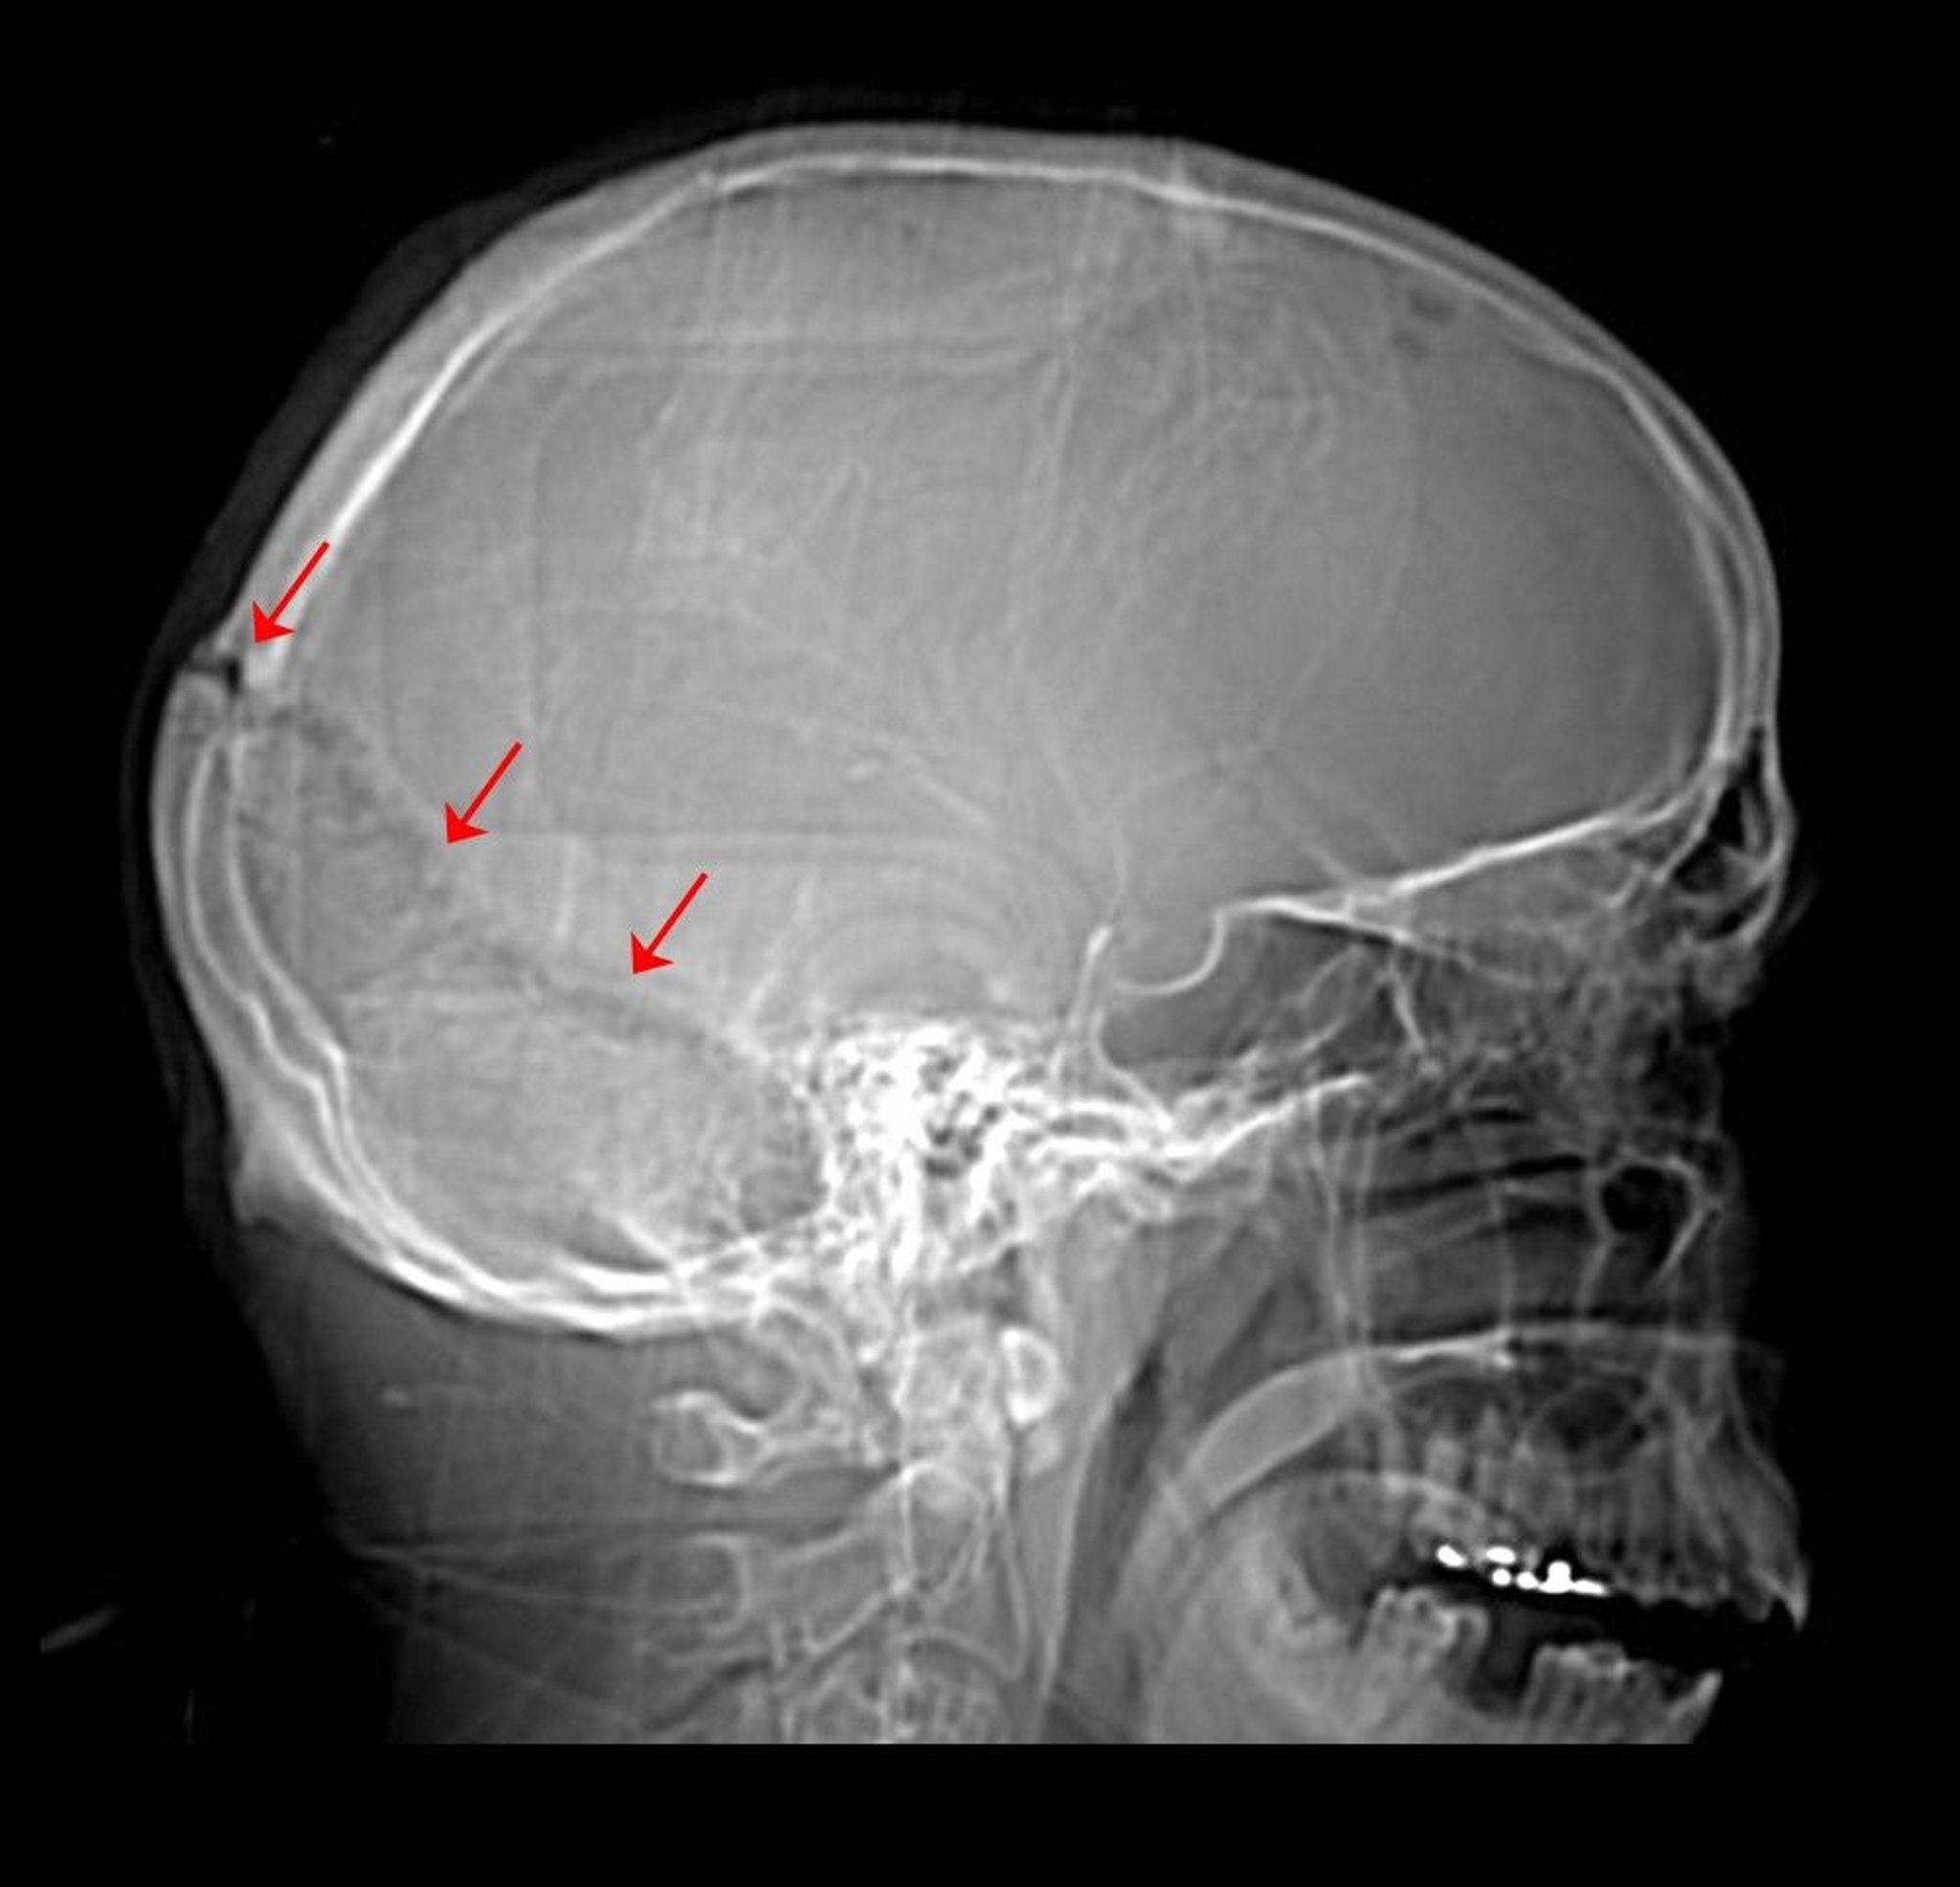

Skull Fracture

This radiograph of the skull shows a fracture of the lambdoid suture.